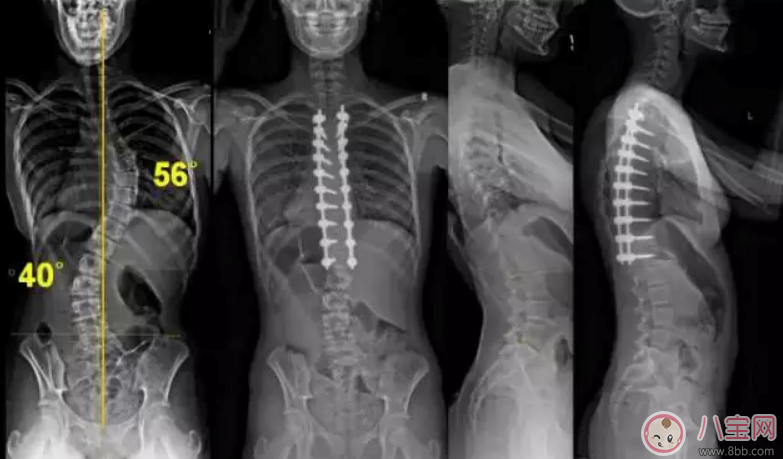

青少年脊柱側彎是青少年的常見疾病,約每 100 個青少年中就有 1~2 個患病(本文中所探討的,主要是青少年特發性脊柱側彎)。若等到孩子畸形重時發現,孩子將錯過最佳的治療時機。

2. 脊柱側彎:顧名思義,脊柱側彎,指正面看,脊柱向左或向右側方彎曲,偏離中線。人體的脊柱是三維結構,那么,脊柱側彎從三維上看,會伴有脊柱結構的旋轉。因此,脊柱側彎是一種三維的脊柱畸形。

最有效的肯定是手術治療,但是手術有個問題,因為要打骨釘什么的,昂貴是一方面,還可能會影響寶寶長高。因此也不是隨便做的,需要先拍片看看生長板,先看看孩子這幾年是不是還在發育期,還會不會長高。如果還會長高,那么手術會推遲。

等寶寶不再長高了,才考慮最手術,手術肯定能解決問題,但這個過程很折騰,如果側彎測度不是特別嚴重,也不建議手術。